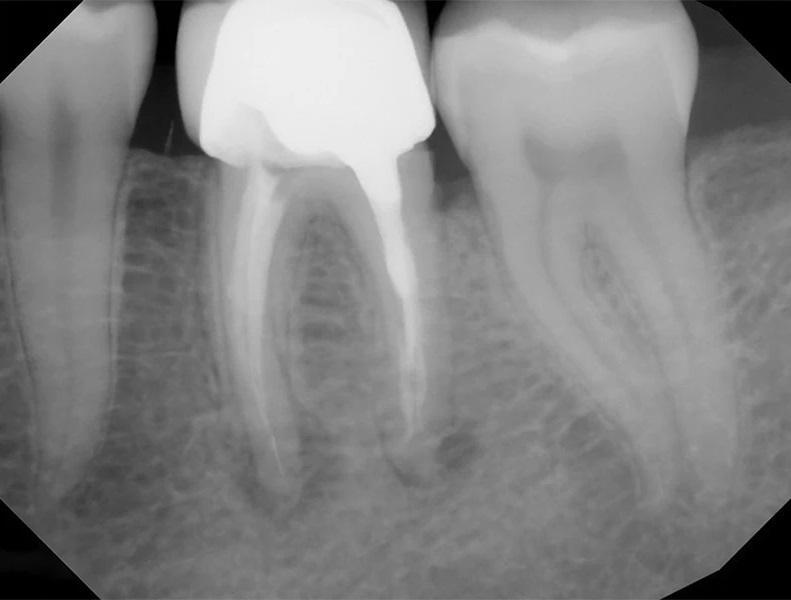

Наличие четко определяемых проблем или технических ошибок при первичном эндодонтическом лечении также играет важную роль в прогнозировании исходов повторного лечения. Исследования показывают, что результаты повторного лечения часто обратно пропорциональны качеству первичного лечения. Когда причины неудачи первичного лечения очевидны и поддаются коррекции (например, пропущенный канал или неполная обтурация), прогноз повторного лечения, как правило, более предсказуем, поскольку возможна целенаправленная коррекция выявленных дефектов (фото 2–5).

Фото 2–5. Клинический случай 2. Выявляемые причины неудачи первичного эндодонтического лечения, как правило, ассоциированы с более предсказуемым исходом повторного лечения.

Фото 2: Предоперационная периапикальная рентгенограмма, демонстрирующая ранее не выявленную анатомию в зубе 36.

Фото 4: Периапикальная рентгенограмма сразу после лечения.